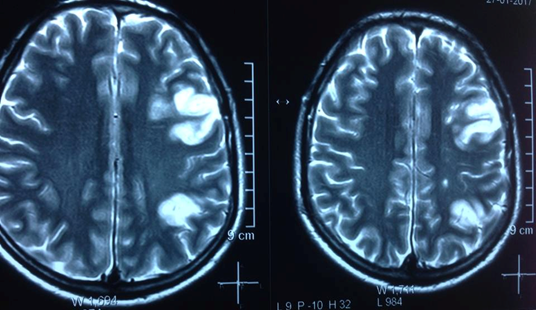

Lãnh đạo Bệnh viện Đa khoa Tâm Trí Nha Trang (Khánh Hòa) cho biết, bệnh viện vừa phát hiện một bệnh nhân bị nhồi máu đa ổ vùng bán cầu não trái, đây là loại bệnh rất hiếm gặp.